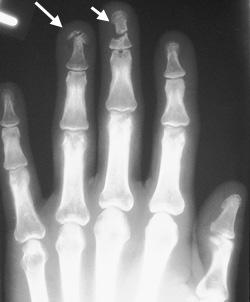

Диагностика перелома фаланги

Как ни странно, но на основании обычного осмотра достаточно сложно установить обычный перелом фаланги пальца без смещения даже весьма опытному хирургу. Дело в том, что все описанные выше симптомы могут возникнуть и при сильном ушибе и при вывихе одного из межфаланговых суставов. Единственным способом на 100% разобраться в ситуации и поставить верный диагноз является проведение рентгенологического исследования.